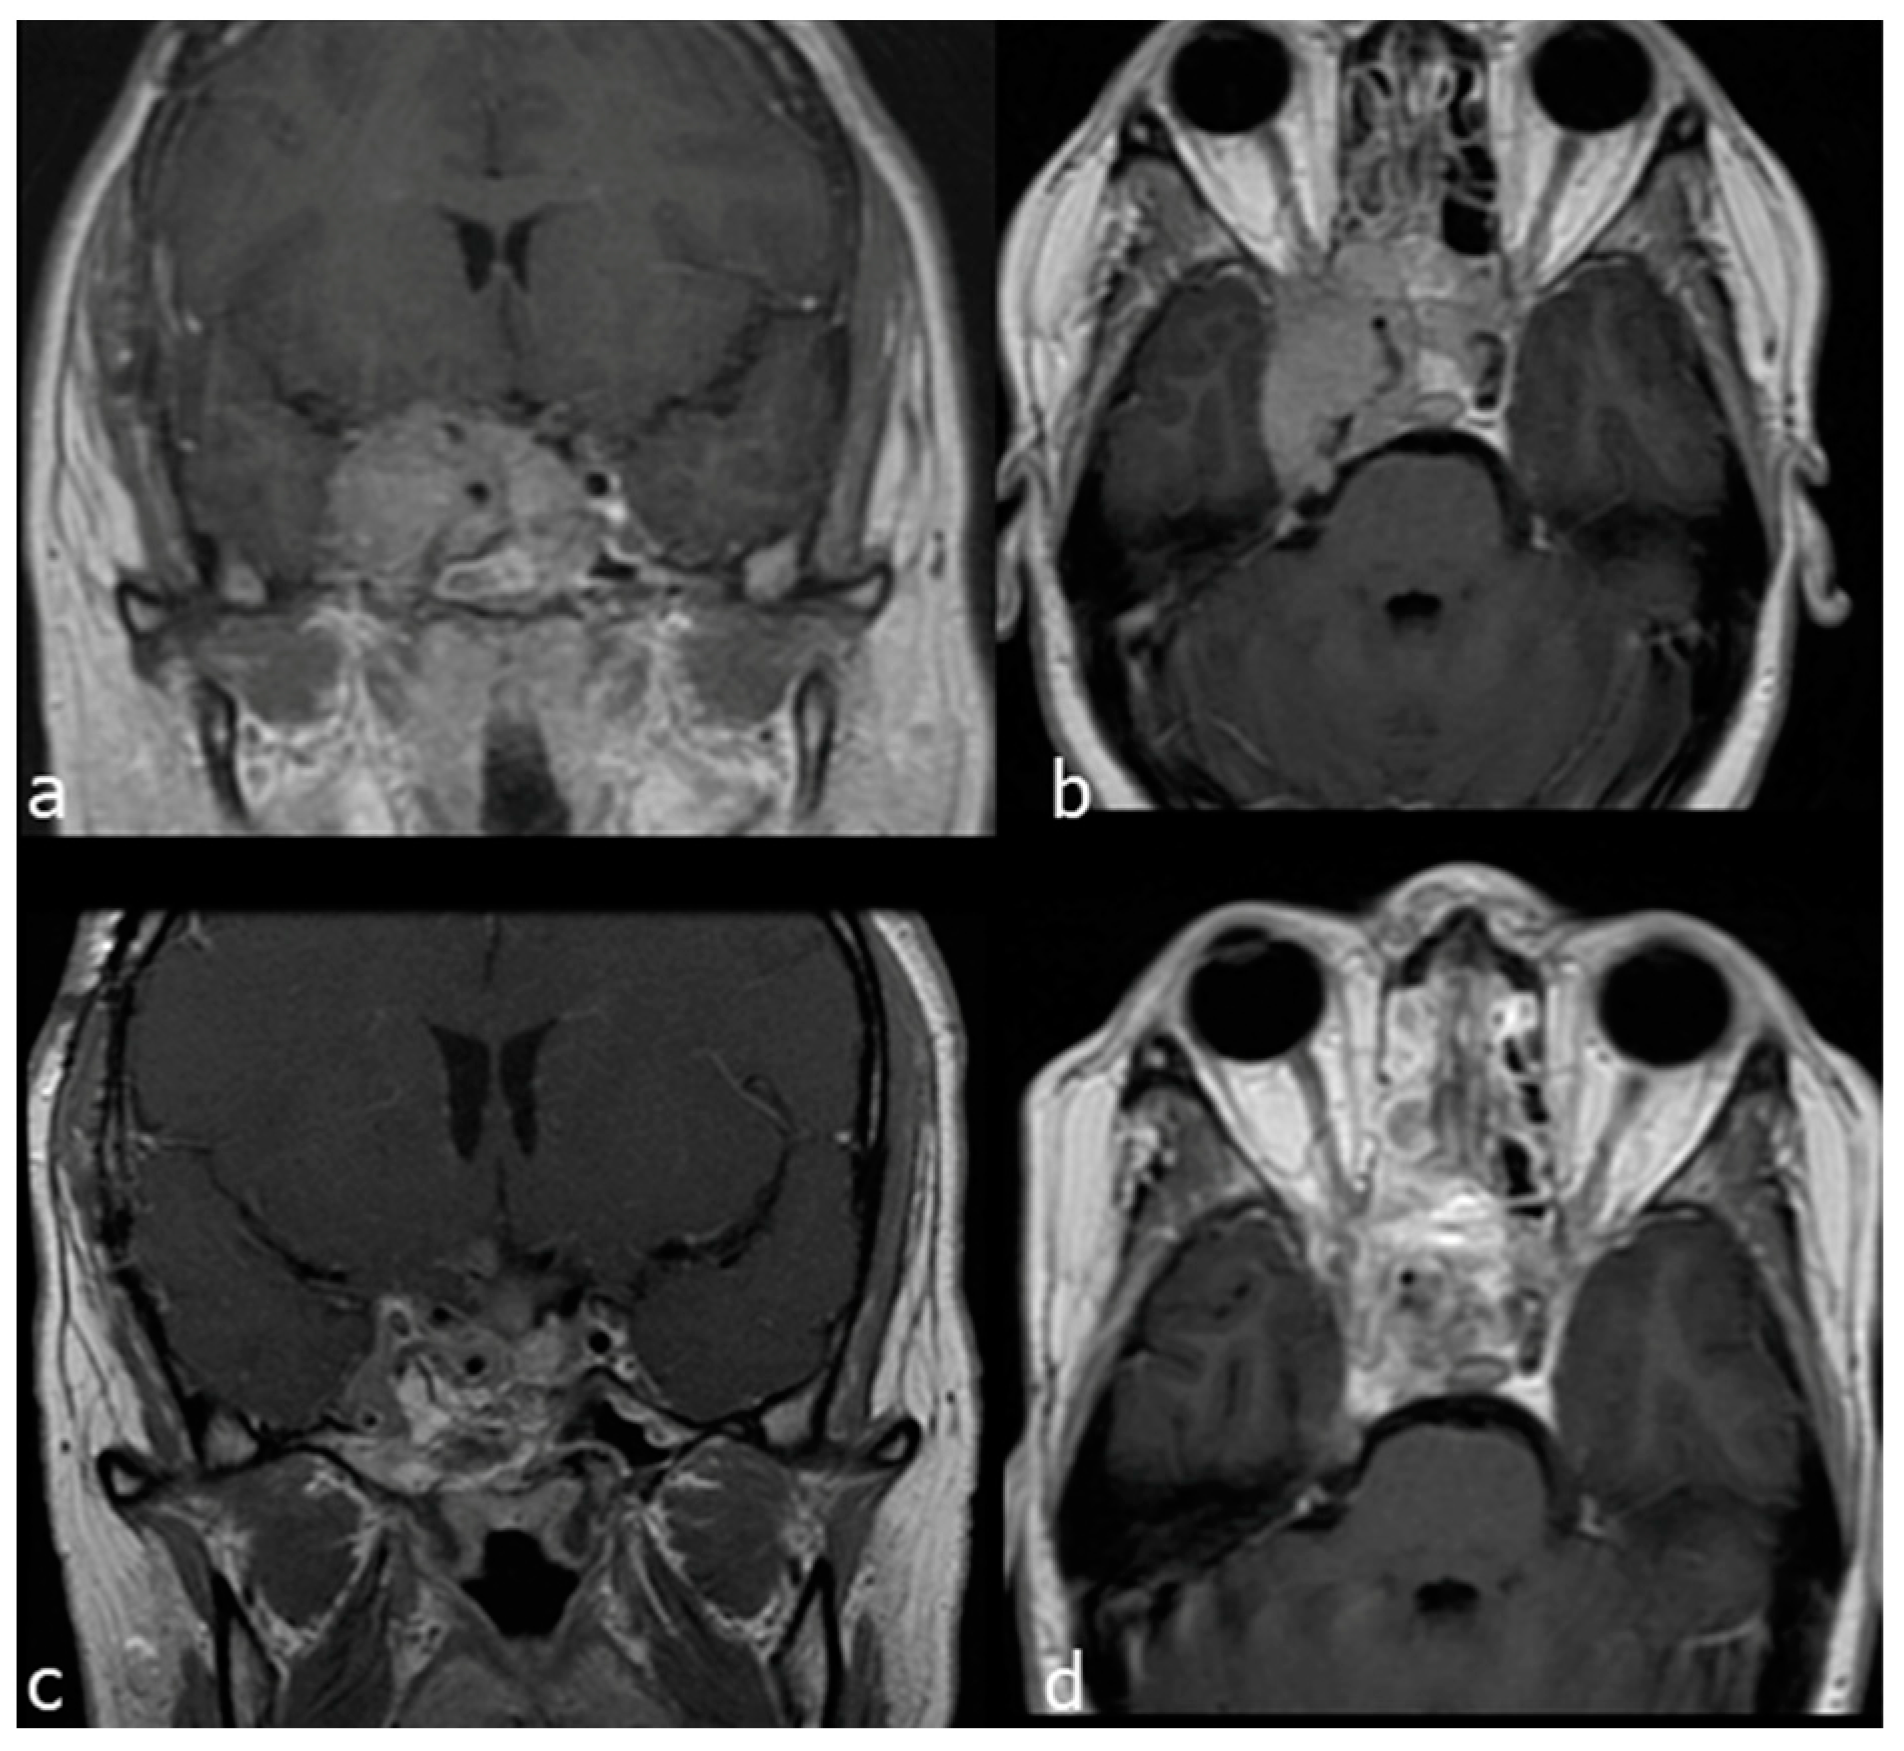

A 28-year-old woman affected by a recurrent giant non-secreting pituitary adenoma, previously operated through transcranial and EEA approaches, presented an extensive invasion of the right cavernous sinus (Knosp grade IV), causing trigeminal compression and facial numbness. She underwent a combined EETC, right trans-pterygoid and CTM approach. An indocyanine green video-angiography was performed intraoperatively to locate the pcICA [21]. The sellar portion of the tumor was removed through the endonasal corridor, and the CTM was exploited to resect the tumour invading the right cavernous sinus, laterally to the cavernous segment of the ICA. A multilayer reconstruction with fat, fascia lata and a right nasoseptal flap was then performed. Near total resection was accomplished (Figure 7).

Figure 7.

Case 2: preoperative and postoperative MRI scans of a recurrent giant non-secreting pituitary adenoma, previously operated through transcranial and then operated on by a combined EETC and CTM approach. (a) preoperative MRI scan, axial view. (b) preoperative MRI scan coronal view. (c) postoperative MRI scan, axial view. (d) postoperative MRI scan, coronal view.

- Case 3

A 39-year-old man affected by a recurrent giant prolactin-secreting pituitary adenoma with clival extension, bilateral cavernous sinus invasion mainly on the right side and displacement of the cavernous segment of the ICA was referred to surgery because of dopamine agonists’ resistance causing tumour growth and visual worsening. He underwent a combined EETC and CTM approach and a right nasoseptal flap was raised for reconstruction. Subtotal resection was achieved by removing the clival and right cavernous sinus tumor components (Figure 8).

Figure 8.

Case 3: preoperative and postoperative MRI scans of a recurrent giant non-secreting pituitary adenoma, previously operated through transcranial and then operated on by a combined EETC and CTM approach. (a) preoperative MRI scan coronal view. (b) preoperative MRI scan, sagittal view. (c) postoperative MRI scan, coronal view. (d) postoperative MRI scan, sagittal view.